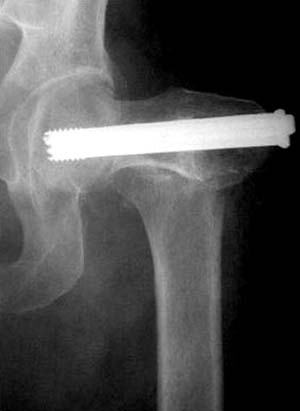

Или всё таки красивее было бы вот так? И при нагрузках динамизация по винту?